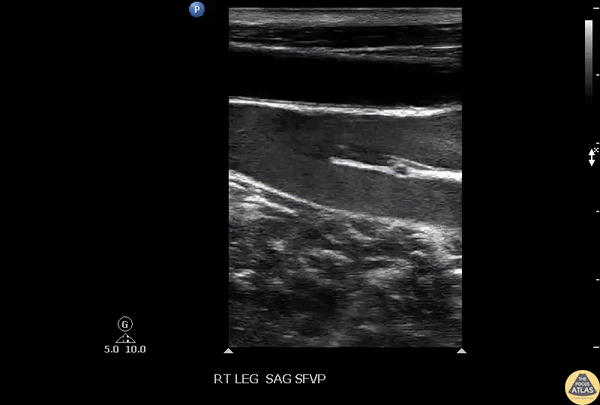

Vascular - Venous Valves

Seen here is healthy appearing venous system with effectively functioning valves. Important distinction between the arterial and venous systems. Image courtesy of Robert Jones DO, FACEP @RJonesSonoEM Director, Emergency Ultrasound; MetroHealth Medical Center; Professor, Case Western Reserve Medical School, Cleveland, OH View his original post here